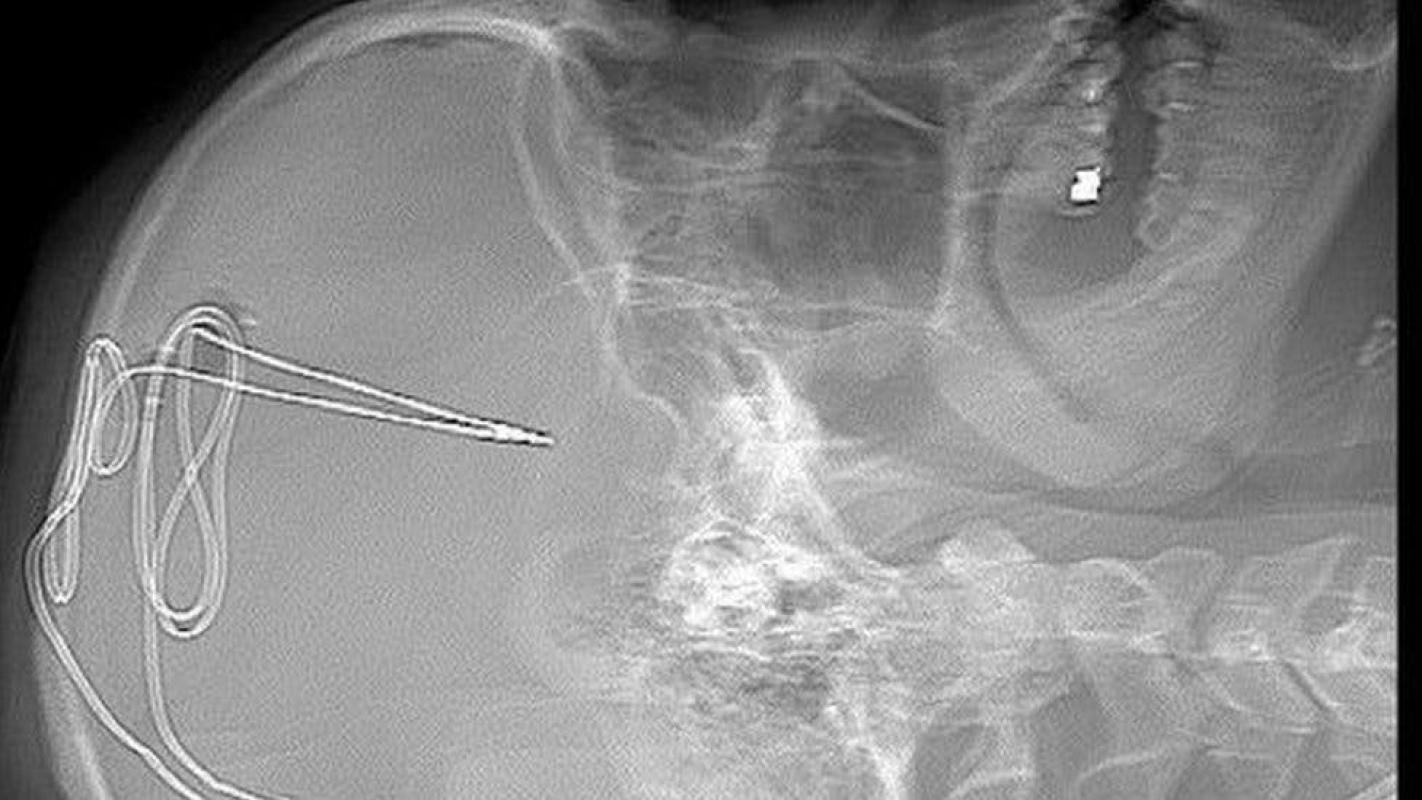

Después se practica la cirugía. Para ello se hace un pequeño agujero en el cráneo para insertar un electrodo de 1 milímetro en un área específica del cerebro que regula impulsos como la adicción y el autocontrol.

Se inserta una batería debajo de la clavícula, de manera que la actividad cerebral se monitorea de manera remota por el equipo de médicos, fisiólogos y expertos en adicción para ver si el anhelo de consumir la sustancia disminuye.